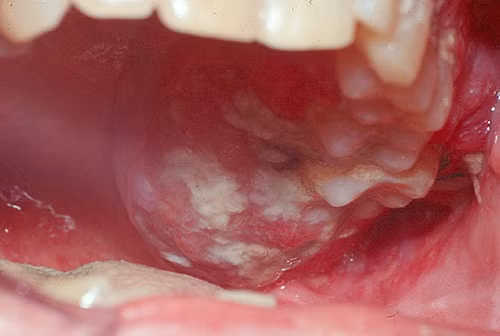

Một trong những triệu chứng thường thấy của ung thư môi là việc xuất hiện các vết loét khó lành, thường ở dạng cục mảng trắng trên môi hoặc vị trí quanh miệng, dễ gây cảm giác đau đớn. Ảnh: vienyhocungdung.